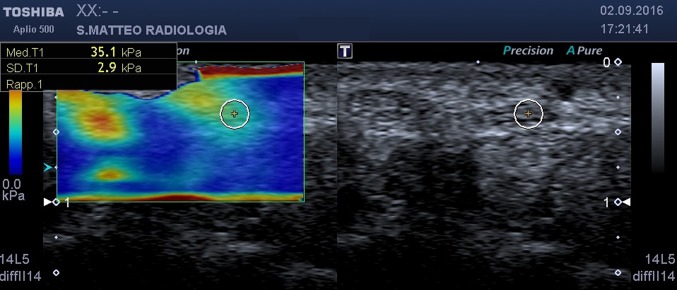

Fig. 3.

SWE, axial scan at carpal tunnel outlet. On the left the b-mode image, on the right the elastogram. The circular ROI encloses the median nerve

at the carpal tunnel outlet (hamate–trapezium level) (Fig. 3).

Using this approach, the values of the stiffness of the nerve at the various sampling points were obtained (Figs. 1, 2, 3). Statistical analysis was performed using MedCalc (MedCalc Software, Ostend, Belgium).